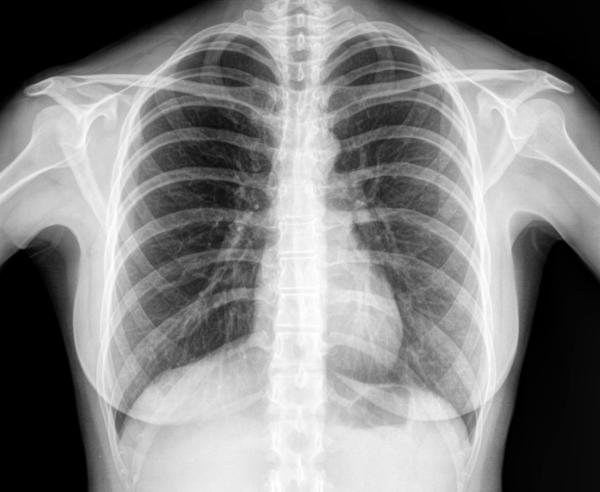

1. Raze X

Razele X sunt primele imagini de diagnostic din lume. Este dificil să ne imaginăm un spital modern fără o astfel de examinare. Aceasta include fluorografie pentru a verifica plămânii noștri și imagini pentru boli articulare sau fracturi osoase. Detectarea precoce a tuberculozei sau a unei tumori în plămâni crește șansele de recuperare. În plus, razele X dure pot distruge celulele canceroase. Principiile radioscopiei moderne sunt utilizate atât în sistemele de securitate (scanere la aeroporturi, gări etc.), cât și în industrie. În metalurgie sau inginerie mecanică, uniformitatea structurii scanate cu raze X indică caracteristici bune de rezistență ale pieselor. În același mod, se verifică rezistența structurilor de beton pentru construcția de locuințe monolitice, cusăturile sudate ale structurilor metalice complexe.

Una dintre cele mai importante invenții care salvează vieți omenești se bazează pe descoperirea lui Wilhelm Conrad Roentgen, un fizician German care a lucrat la Universitatea din Würzburg la sfârșitul secolului al XIX-lea. Radiația pe care a descoperit-o a fost numită după el și mai târziu clasificată ca unde electromagnetice în intervalul dintre radiațiile ultraviolete și gamma. În acel moment, nu se știa că astfel de unde scurte se formează atunci când electronii accelerați sunt decelerați brusc în momentul coliziunii lor cu atomii substanței anodice. Descoperirea a fost întâmplătoare: în 1895, Wilhelm Conrad Roentgen, studiind strălucirea în tubul catodic, a văzut dintr-o dată că, simultan cu pornirea sau oprirea aparatului, lumina începe să apară sau să dispară pe un carton întins lângă el, acoperit cu cristale de bariu platinocyanide. În același timp, tubul catodic a fost înfășurat în hârtie groasă neagră. Pornind și oprind tubul catodic, omul de știință a concluzionat că servește ca o sursă de radiații atotpătrunzătoare, ceea ce face ca cristalele sensibile de platinocianură de bariu să strălucească.

Continuând să studieze razele X, radiografia a primit pe echipamentul său prima imagine a scheletului osos-mâna. De atunci, elementele de bază ale unei convențional cu raze X s-au schimbat puțin: un catod (X-ray) tub, un dispozitiv de alimentare (două transformatoare) , și un film-fotografie de hârtie făcute din argint compuși cu halogeni, care întuneca cu intensitate diferită în funcție de densitatea a transmis materialul și forma, astfel, o imagine.

În 1917, legea exponențială a atenuării radiațiilor în substanțe a fost aplicată analizei imaginilor cu raze X, care au arătat o precizie ridicată. Aceasta a dus la apariția tomografiei computerizate (raze X tridimensionale)-un studiu strat-cu - strat al țesuturilor și crearea unei imagini ținând cont de diferența de absorbție a radiației cu raze X de către diferite țesuturi în densitate. Inventatorii tomografiei sunt americanul Allan Cormack, care a dezvoltat un algoritm matematic pentru reconstrucția imaginii tomografice în 1963, și britanicul Godfrey Hounsfield de la EMI Ltd. Britanicul, folosind algoritmul Cormack, în 1971 a creat primul tomograf cu raze X pentru scanarea creierului. În 1979, ambii au primit Premiul Nobel pentru dezvoltarea tomografiei computerizate. Tomograful oferă un diagnostic mai precis al organelor individuale și este deosebit de important pentru determinarea bolilor creierului și vaselor de sânge. Multe vieți au fost salvate datorită determinării infailibile a tipului de accident vascular cerebral folosind tomografie computerizată, care este încă considerată o condiție importantă pentru diagnosticarea unei astfel de boli.